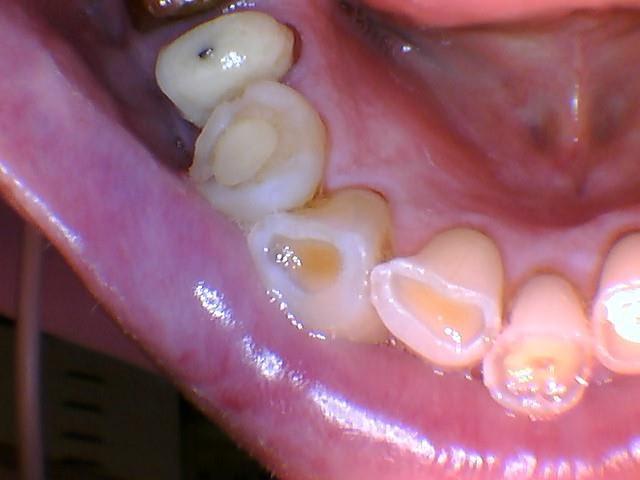

Pour info, les photos sont réalisées avec une caméra made in China.

Bon sérieusement , c'est toi qui va couler ton cabinet en "dépannat" ce patient qui veut du rapide . je plaisantais avec des coiffes acier mais bon , tu as vu l'état d'usure des céramiques .

c'est pas un bruxomane ton gazier : c'est de l'érosion.